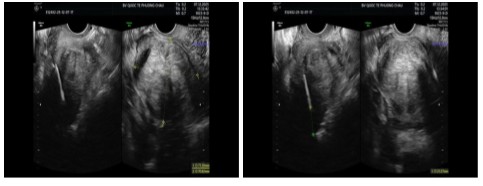

- Kết quả siêu âm: thành sau tử cung có nhân xơ tử cung kích thước to # 71 x 71 mm, nằm gần cổ tử cung. Đây là vị trí “khó”, có nguy cơ phải phải phẫu thuật cắt tử cung - Đây cũng là điều khiến chị T lo lắng vì chị mong muốn bảo tồn tử cung.

Hình: Thành sau tử cung có nhân xơ tử cung kích thước to # 71 x 71 mm, nằm gần cổ tử cung

(Nguồn: Bệnh viện Quốc tế Phương Châu)

Hình: Thực hiện phương pháp RFA điều trị nhân xơ tử cung